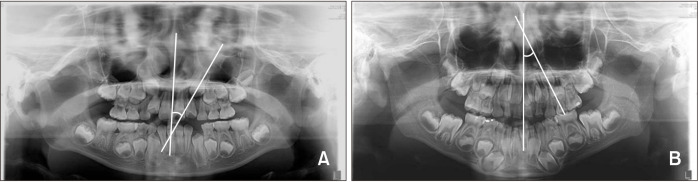

Abstract Image